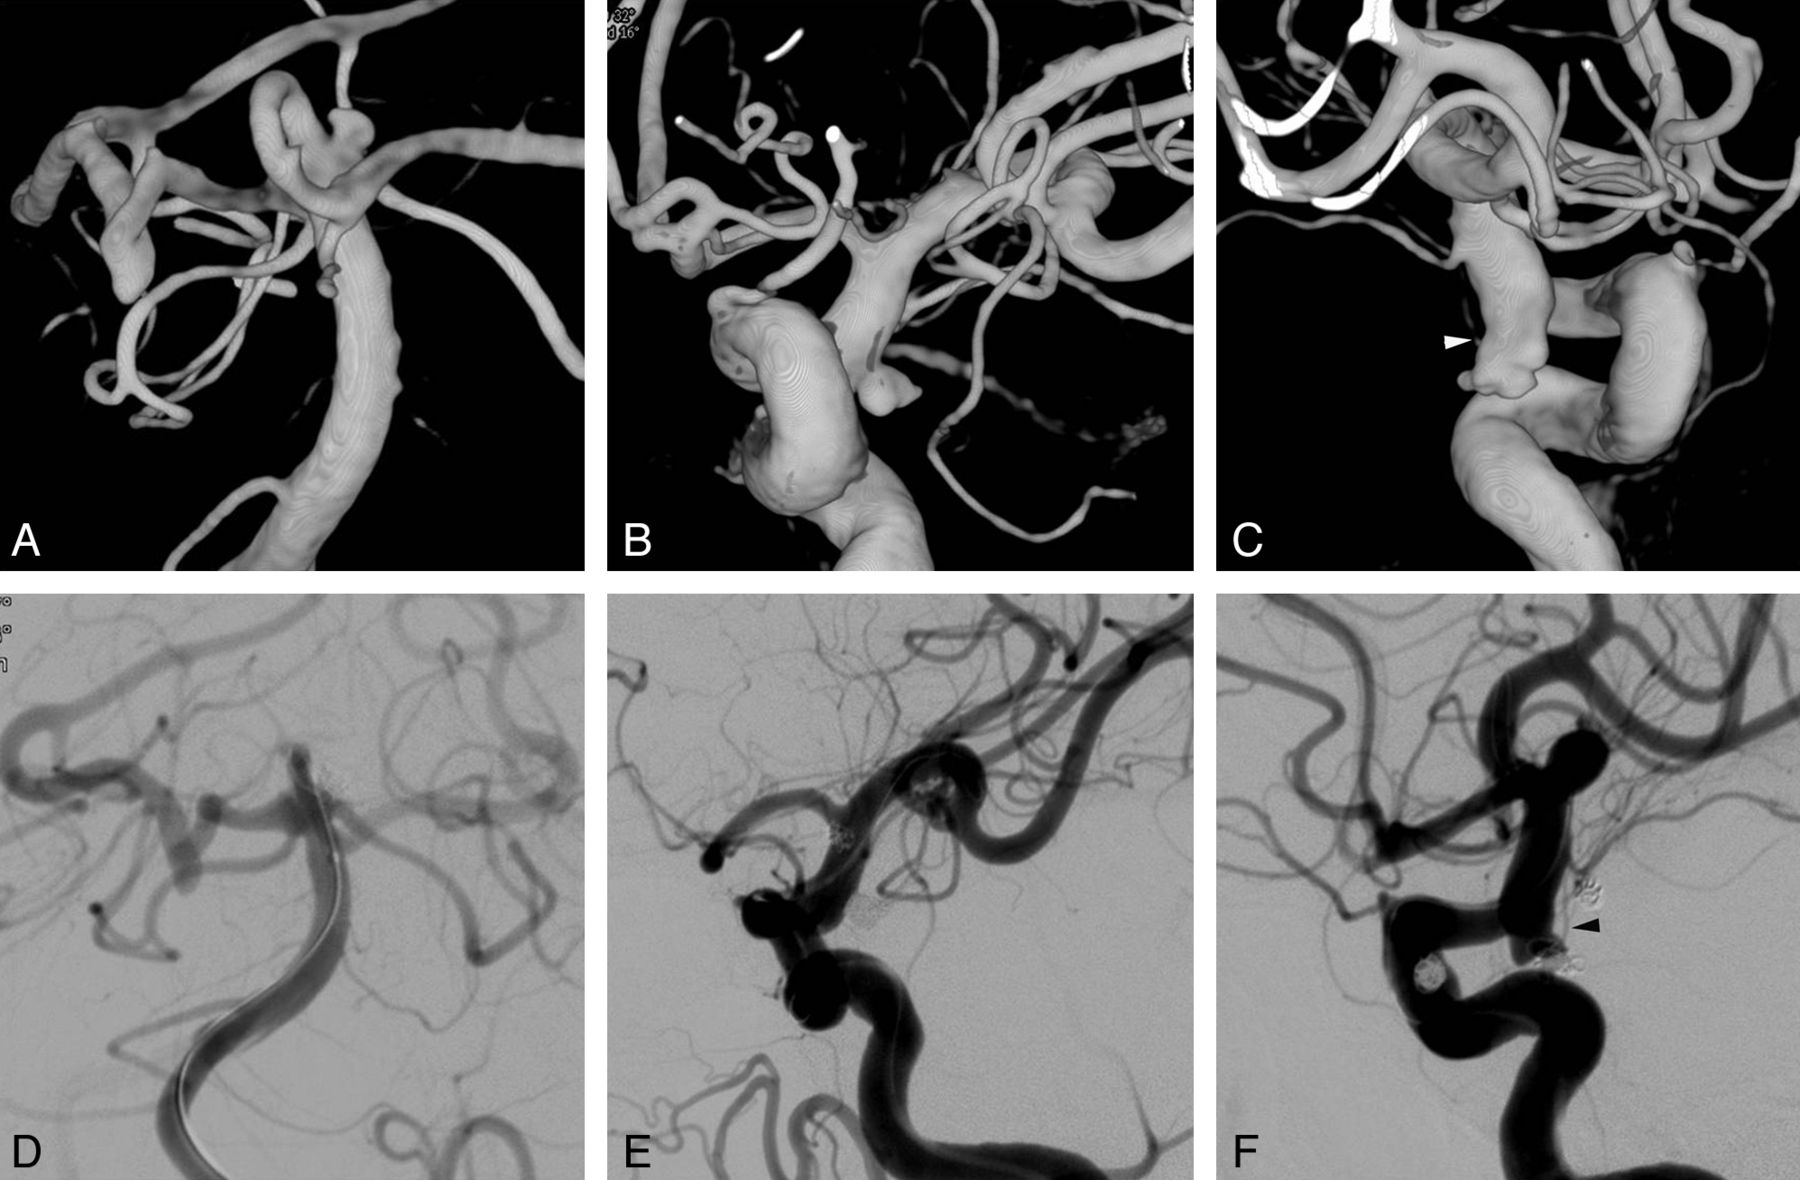

In patients with SAH who had multiple aneurysms and in whom it was unclear which aneurysm was ruptured, 1-stage coiling for all of the possibly ruptured aneurysms, regardless of the distribution of multiple aneurysms, was an important advantage (Fig 1). In patients with unruptured aneurysms, multiplicity is associated with a greater risk of rupture compared with single aneurysms.17 Which patients with unruptured aneurysms will experience SAH is often unpredictable, and it is even more difficult to determine which of the multiple unruptured aneurysms will rupture. In our institution, 3 patients had SAH from a remaining aneurysm after the most dangerous-looking aneurysms had been treated (data not shown). Therefore, it is our policy to treat, if feasible, all unruptured aneurysms in patients in good medical condition. Because coiling of unruptured aneurysms is associated with less morbidity and mortality than clipping,18 it seems reasonable to treat as many aneurysms as possible with coiling.

A 61-year-old woman presented with a Hunt and Hess scale grade 3 subarachnoid hemorrhage. Nonenhanced CT (not shown) showed a diffuse, nonlocalized, subarachnoid hemorrhage in the entire basal cistern. 3D reconstruction images of cerebral angiography reveal 3 similar-sized small aneurysms at the left superior cerebellar artery origin (A) and bilateral posterior communicating artery origin (B and C). Each of the 3 aneurysms also has an irregular shape with a daughter sac. The white arrowhead indicates a left tuberothalamic artery incorporated into the aneurysm sac. Postembolization control angiograms after balloon-assisted coiling for all 3 aneurysms show complete occlusion of the superior cerebellar artery (D) and the left posterior communicating artery (E) aneurysms, and an intentional neck remnant, from which a left tuberothalamic artery (black arrowhead) directly originated, of the right posterior communicating artery aneurysm (F).